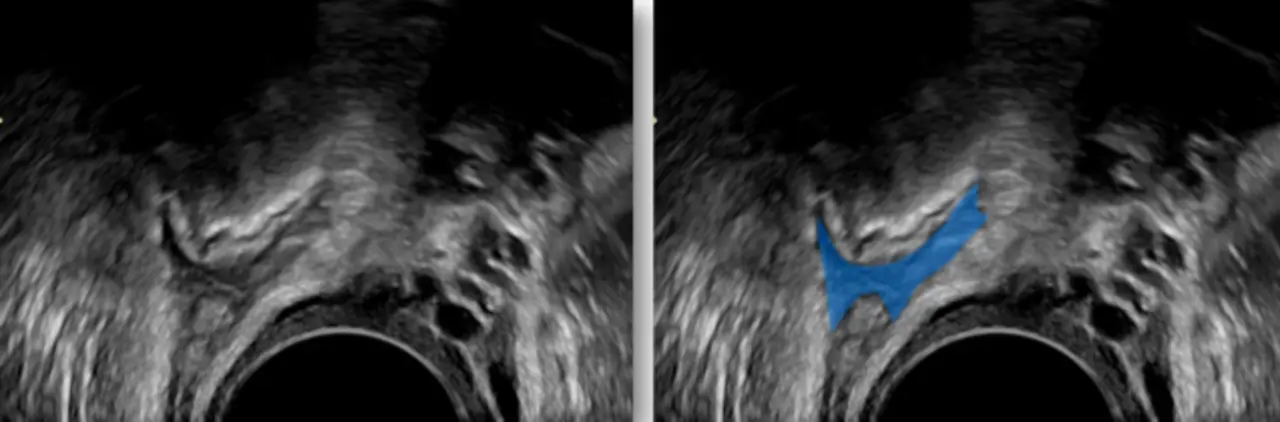

Aktuell zeigt der Algorithmus die Endometriose-​Herde bereits durch farbige Markierungen bei 2D-​Ultraschallaufnahmen an. Läuft die Entwicklungsarbeit wie gewünscht, hoffen wir, bis Ende des Jahres ein 3D-​Modell der Gebärmutter zu generieren, auf dem alle Wucherungen und Verwachsungen deutlich markiert sind. So könnten Gynäkologinnen und Gynäkologen die Endometriose-​Herde genau lokalisieren und die Schwere der Erkrankung besser einschätzen.

Ein Ultraschallbild mit farblich markierter Endometriose.